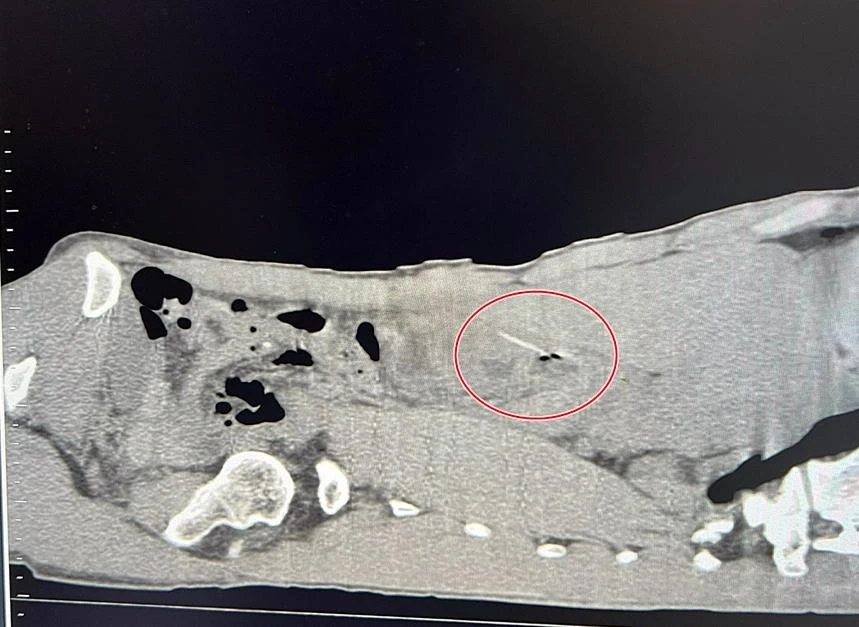

Dị vật tăm tre trong ổ bụng bệnh nhân (vòng đỏ). |

Theo gia đình, trước khi nhập viện hai ngày, bệnh nhân thấy đau bụng ở vùng thượng vị nên tự mua thuốc uống nhưng không giảm nên nhập viện điều trị. Các bác sĩ ở khoa Ngoại tổng hợp, Bệnh viện Đa khoa tỉnh Bình Thuận đã tiến hành siêu âm và ghi nhận có dị vật.

Sau đó cho chụp CT vùng bụng bệnh nhân thì phát hiện dị vật đâm xuyên qua tá tràng. Qua hội chẩn, bệnh viện quyết định mổ cấp cứu bằng phương pháp nội soi, phát hiện dị vật là cây tăm xỉa răng đã đâm thủng tá tràng; thủng luôn túi mật và gây viêm phúc mạc.